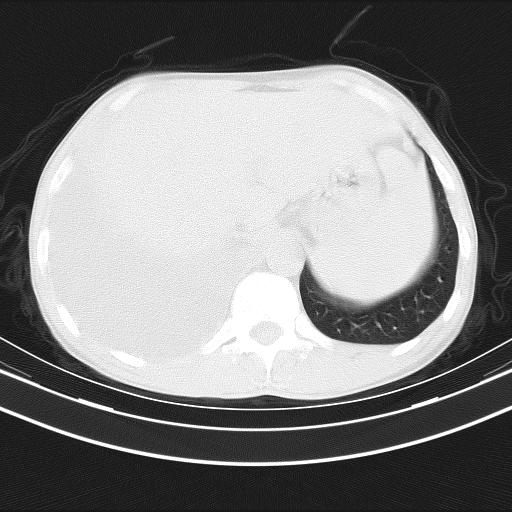

男性,44岁,结核病史多年。现胸闷气短,咳嗽,偶咳血。

右侧胸腔积液

右肺下叶不张

双肺多发结节影最分空洞形成考虑占位不除外结核

双肺陈旧性病变

1、右侧大量胸腔积液伴右肺压缩性膨胀不全,建议抽液治疗后复查 2、两肺继发性tb伴空洞形成。

1)两肺继发性肺结核伴空洞形成,左肺多发性结核球。2)右侧大量胸腔积液伴右肺部分膨胀不全。3)纵隔淋巴结肿大。

1,双肺多发结节 并空洞影改变, 左侧胸腔积液并部分包裹, 结合原病史首先考虑结核. 但也不除外其它.

2,左侧有一根肋骨陈旧性骨折? 建议追查 .

吉大一院胸水抽检结果:结核性胸水